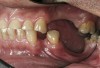

Initial examination revealed a partial edentulous patient with extensive wear of the maxillary anterior teeth and moderate wear in the mandibular teeth (Figure 1, Figure 2, Figure 3 , Figure 4, Figure 5, Figure 6 and Figure 7). The patient's maxillary and mandibular RPDs also showed excessive wear and multiple signs of fractures (Figure 2 and Figure 3). The patient had been wearing a mandibular nightguard for 8 years.

Figure 3  Intraoral occlusal view of mandibular dentition with the existing removable prosthesis presenting excessive signs of wear.

Figure 3